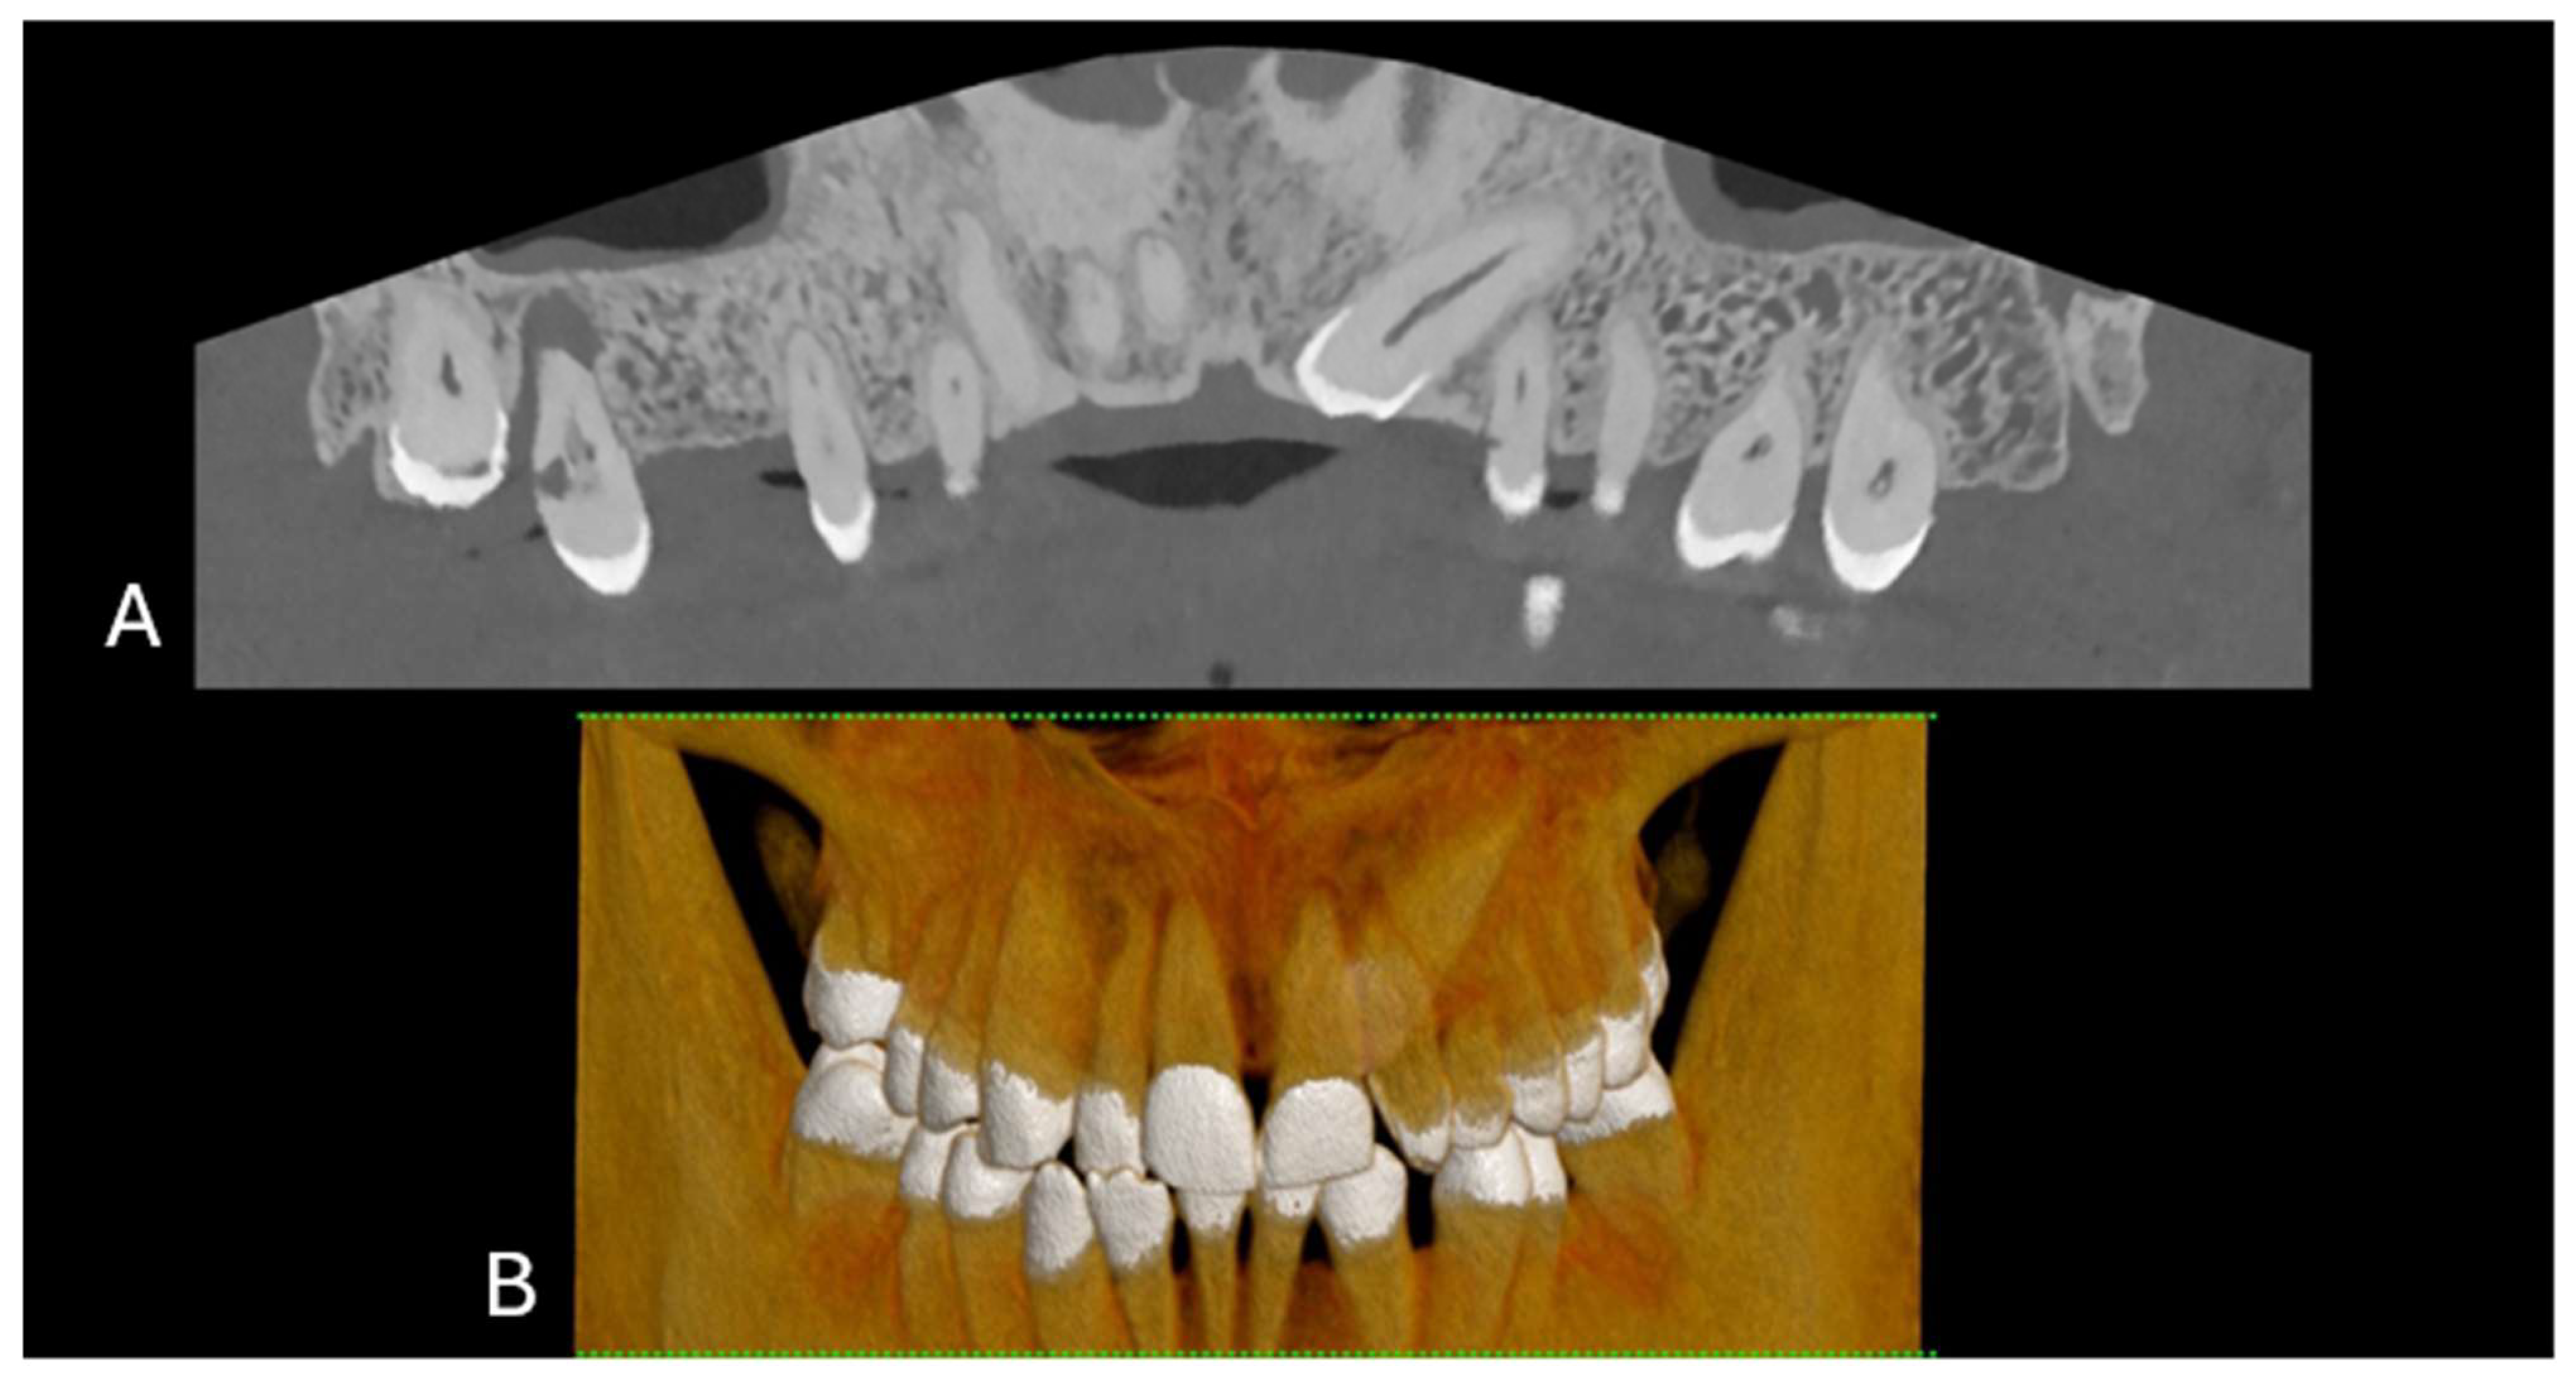

Figure 1. (A) A 3D cinematic rendering of the occlusal view of the lower jaw, where the crowns of molars and premolars are visible. (B) Longitudinal MPR and axial cross-section of upper and lower jaws. (C) The region of a single tooth and root structure in relation to the jawbone. The scan was performed on a commercial whole-body Dual Source Photon Counting CT scanner (NAEOTOM Alpha, Siemens Healthineers, Erlangen, Germany); 0.2 mm slice thickness, 0.1 mm reconstruction increment, FOV 140 mm, spiral acquisition with tube current modulation; resolution matrix of 1024 × 1024 pixels on the source axial reconstructions with a kernel filtering of Bv72; maximum intensity of Quantum Iterative Reconstruction (QIR 4). The actual displayed resolution is 0.1 mm (100 microns). Abbreviations: 3D, three-dimensional; MPR, multiplanar reconstruction; FOV, field-of-view.

The evolution of CT technology has paralleled advancements in computer science, X-ray production, and detection, culminating in novel applications, such as dual-energy CT (DECT) for medical imaging [1]. A significant leap has been made with the introduction of energy-resolving photon-counting detectors (PCDs), which are distinguished by their ability to discern the energy of individual X-ray photons, offering improved spatial resolution, noise reduction, dose efficiency, and spectral imaging [1]. The introduction of clinical photon-counting CT (PCCT) systems in 2021 has led to significant advancements in CT technology, offering the potential for lower patient doses and higher spatial resolution owing to smaller detector pixels [2,3,4,5,6]. This innovation is poised to update clinical applications, particularly in anatomical imaging, by providing clearer images of dental structures (5). PCCT promises to provide high-resolution images (up to 100 µm), superior soft-tissue contrast, and faster scanning times, which are crucial for detailed dental diagnoses and treatment planning (Figure 1 and Figure 2).